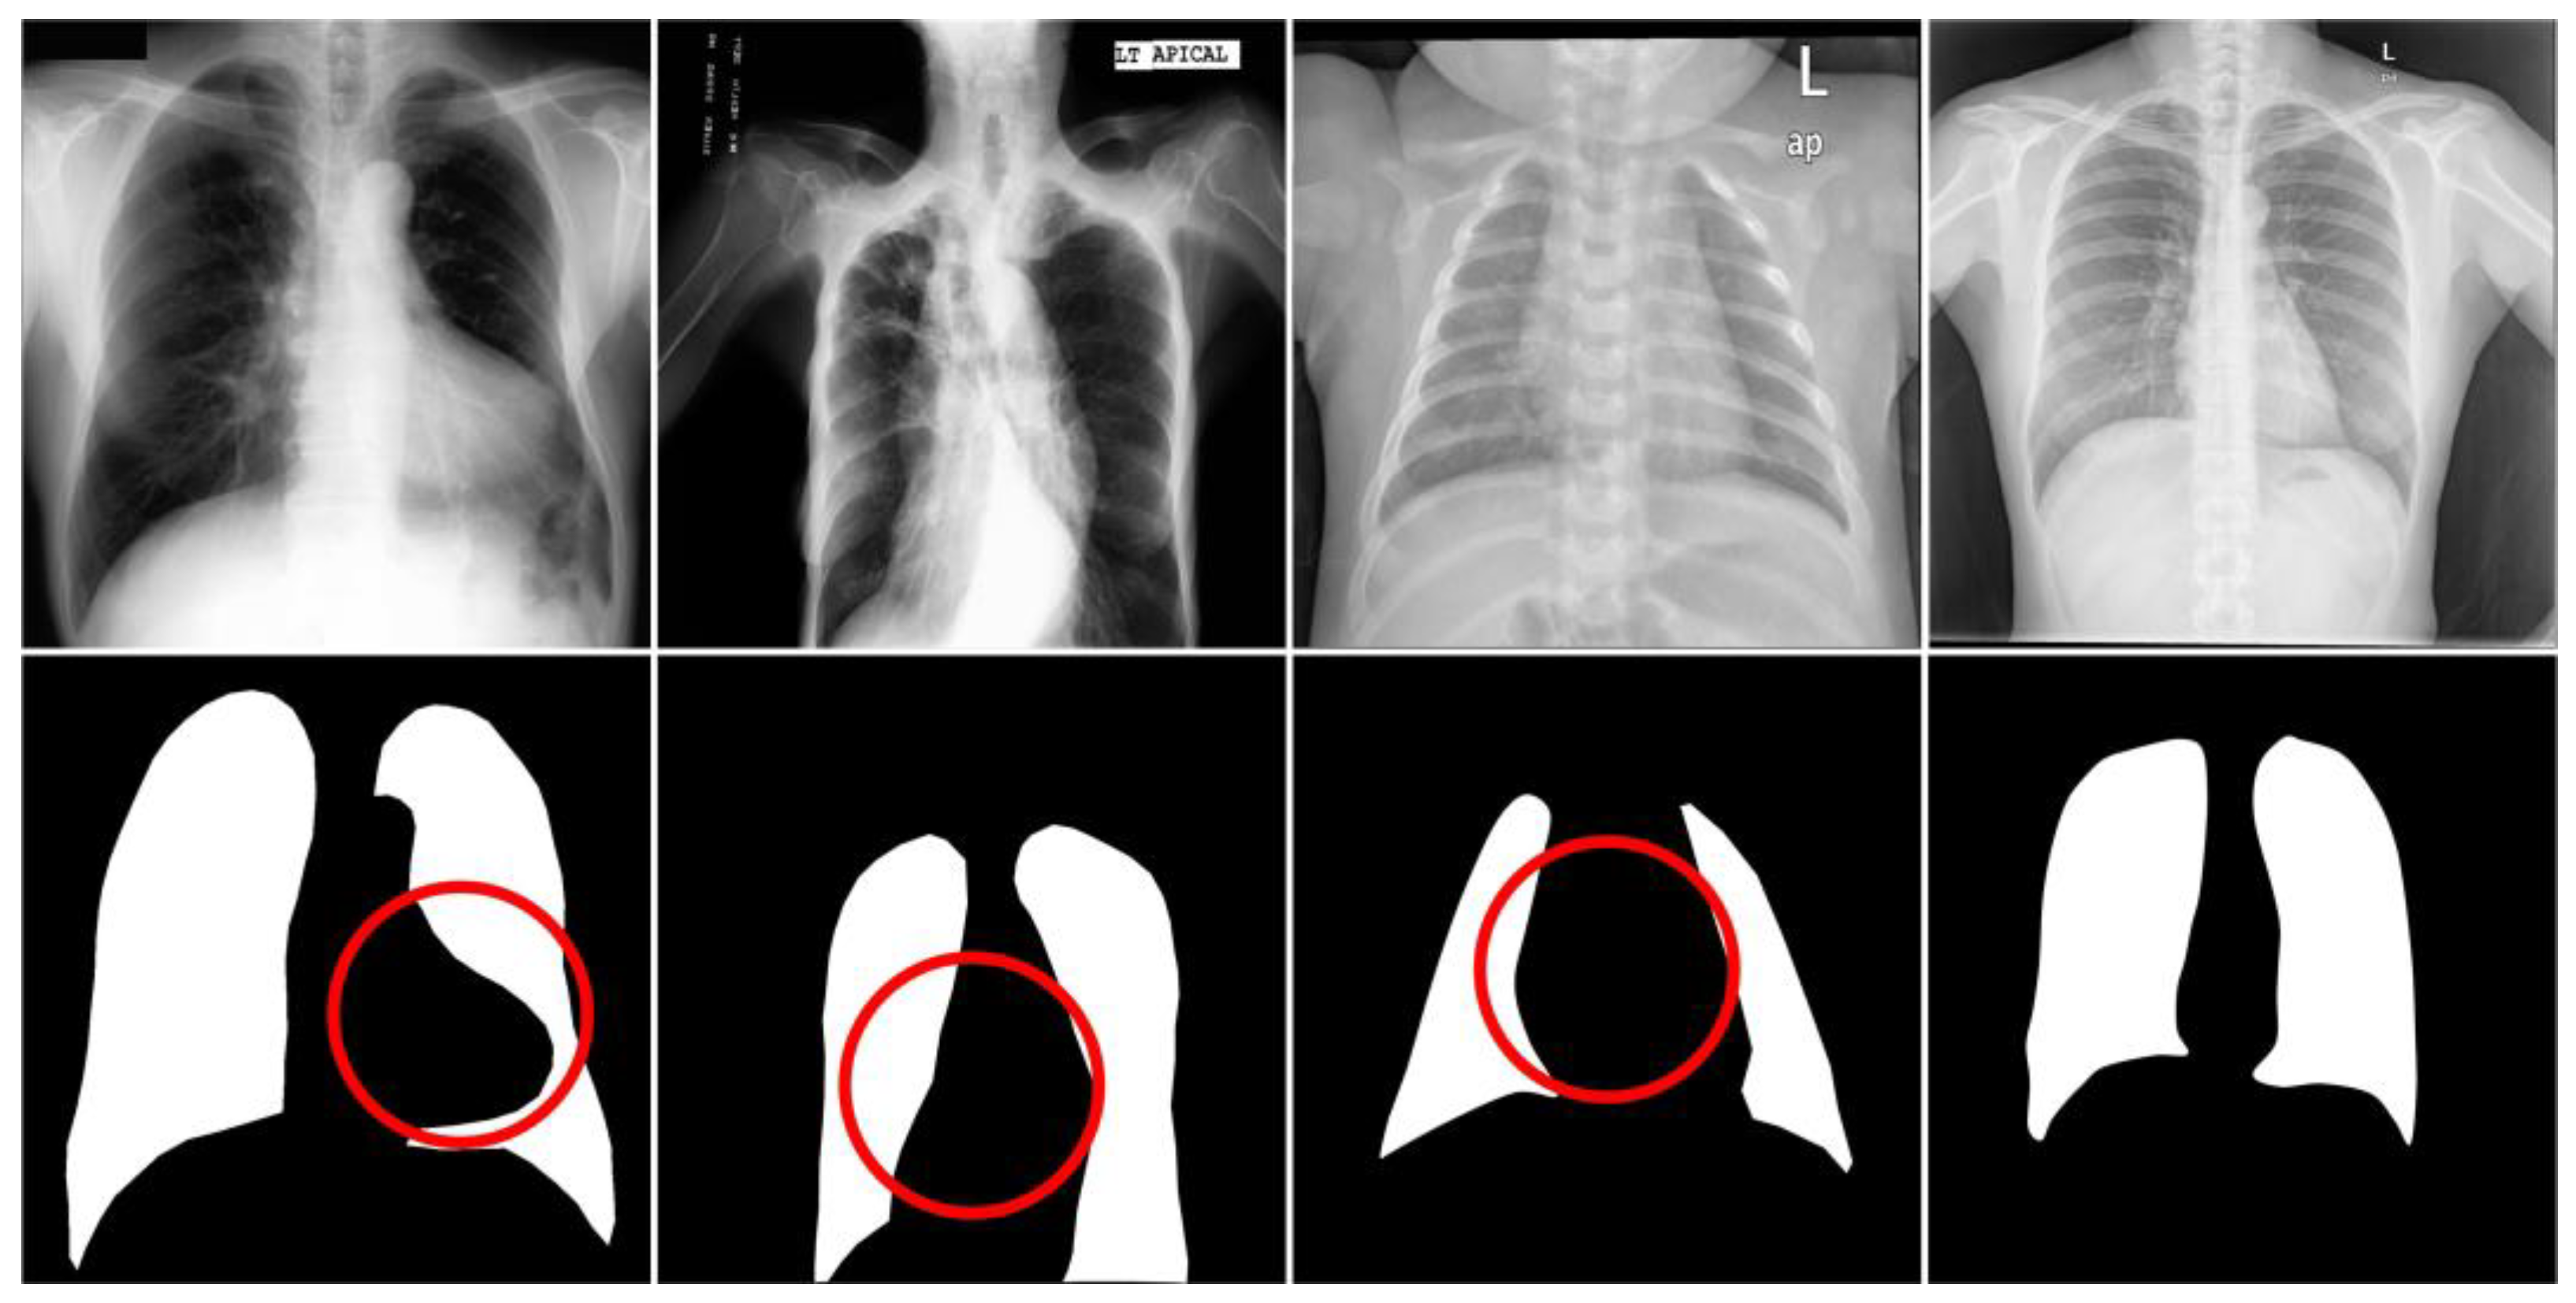

Discussion. Although our proposed method can dynamically aggregate contextual semantic information to obtain better accuracy in medical image segmentation, it still has two limitations. We found that the method we designed was not effective in segmenting image data with strong interference and a small lung field region. As shown in Figure 10, these were the visualized images with different noise disturbances obtained from each of the three datasets, JSRT, MC, and Shenzhen. We can see that, in the lung field region, the area where the lung edges were connected to the organs and bones often contained white noise, which caused great interference to our segmentation and led to a decrease in the segmentation accuracy of individual data, thus affecting the overall segmentation accuracy. In the first column of the dataset of images from the JSRT, we can clearly see that in the lower-right region of the lung field that there was a large area of white noise, and this phenomenon may have been due to the unclear chest region image caused by different acquisition devices or occlusion; the white noise had very small differences with the bones, which easily led to the under-segmentation phenomenon of the model and thus affected the overall performance in the comprehensive assessment. In the second column of the MC dataset images, we can see that the white noise was concentrated in the spine region, which may have been caused by the distance of the patient from the sampling device; due to this interference, it made it difficult for the model to define the boundaries of the lung field region, which was more prone to the under-segmentation phenomenon. In the third column of the Shenzhen dataset images, we found strong white noise overall, and the organs in the middle of the chest region (heart, etc.) also produced strong interference, which caused the overall segmentation performance to degrade. In contrast, the segmentation accuracy was maintained for the rightmost image with lower interference. In addition, our proposed method, due to the high network complexity, was slow for high-resolution processing, and the semantic segmentation network performed pixel-level classification of the input image, which was slow and may not have been suitable for application scenarios with high real-time requirements. In the future, we will design a network that can analyze accurate edge information while obtaining more semantic information, and prune and optimize the network backbone to maintain high accuracy while making the network more lightweight. In the figure, the red circles represent the areas where the data set received interference.

Figure 10.

Segmentation noise interference visualization images for JSRT, MC, and Shenzhen datasets.